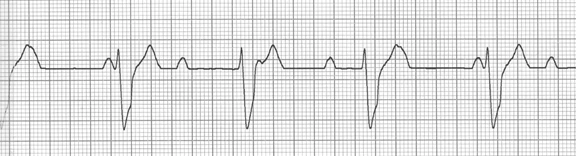

You are working on the telemetry unit. You have just received a patient from the emergency department who presented with syncope of unknown cause. They were unable to discover the cause in the emergency department and the decision was made that she be admitted for additional diagnostics and observation. You just finished her initial assessment, which was unremarkable, and left her room to begin catching up on your charting. The monitor technician hands you the following strip.

This rhythm is called a:

• Third degree AV block.